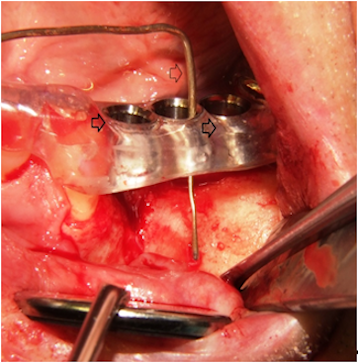

The proposed recipient site for the graft was exposed prior to graft harvest in all cases. In this manner, the dimensions and morphology of the bony defect were measured, and minimal time elapsed between graft harvest and placement (Figure 1 [Fig. 1]).

Figure 1: The figure is showing the left maxilla with alveolar ridge atrophy in region 24 to 26 (FDI tooth numbering system). A splint with integrated tubes which are indicating the planed implant position (black arrows) is fixed on the remaining dentition [11]. The probe (white arrow) is indicating the position and amount of bone which is needed for later sufficient implant placement.